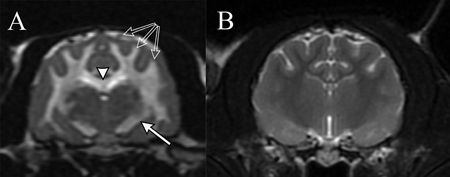

In such cases, magnetic resonance imaging (MRI) of the brain can provide valuable information regarding intoxication. T2-weighted MRI sequences can disclose marked hyperintensity of the CNS white matter as a result of edema (Figure 4). In addition, cytotoxic edema and intramyelinic edema may be observed using an MRI sequence called diffusion weighted images (DWI) and apparent diffusion coefficient (ADC) maps. White matter hyperintensity on DWI and hypointensity on ADC maps strongly support intramyelinic edema (Figure 5). Although not pathognomonic, taken together, neurologic dysfunction and MRI findings suggestive of intramyelinic edema provide strong evidence of bromethalin intoxication.

Figure 4. (A) A transverse T2-weighted image of the cerebrum at the level of the thalamus of a cat with bromethalin intoxication. The white matter of the corpus callosum (arrowhead), corona radiata (open arrows) and internal capsule (closed arrow) shows severe hyperintensity (white) consistent with edema. The topography of the MRI abnormalities exactly matches the topography of the histology. (B) A transverse T2-weighted MRI from a cat with a normal brain. Note that the white matter is normally hypointense (dark). Photo courtesy of Drs. James Hammond and Jennifer Perkins.